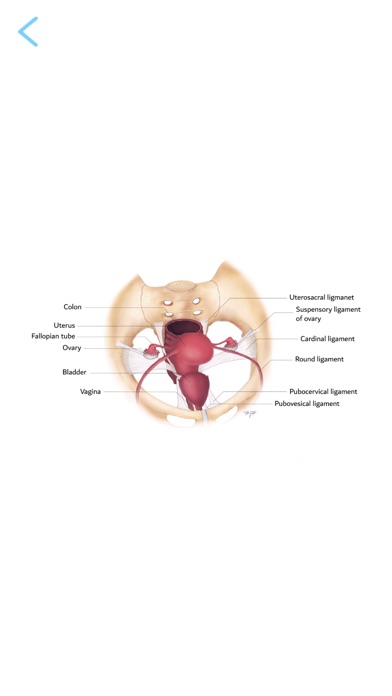

- learn mode: Annotated illustrations of the female pelvis correlated with MRI scans

- test mode: Test yourself using the interactive MRI examinations with highlighted anatomical structures